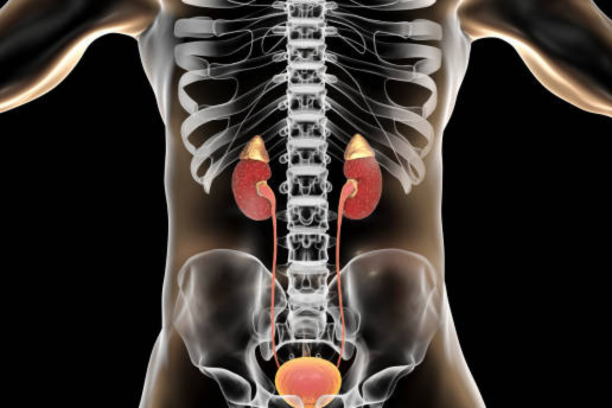

Acute and chronic kidney diseases

Kidney diseases are categorized into two types: acute and chronic, both requiring timely diagnosis and management to maintain optimal kidney function.